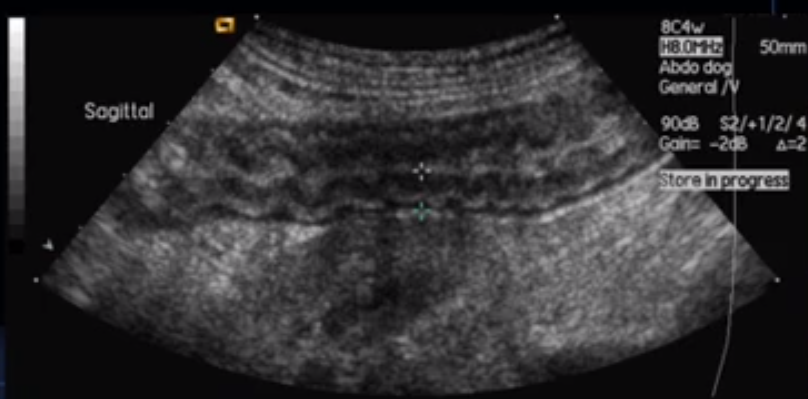

What does this image show?

Corrugated intestine shows hypermotility. Kidney can be seen below.

Descending duodenum. Whiter (hyperechoic or more echogenic) line = R limb of pancreas